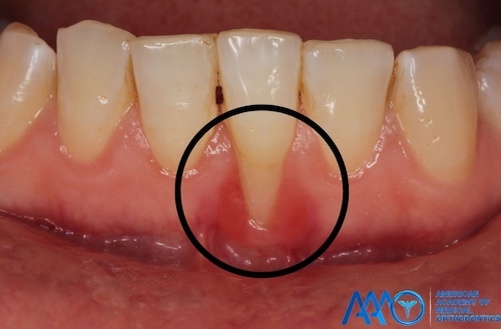

Рецессия десны

Один из главных аргументов для «необходимости правильного прикуса» — рецессия дёсен. В реальности она имеет четыре основные причины:

• Воспалительно-инфекционно-гигиеническая (парадонтит, пародонтит). Развивается воспаление тканей десны, а через некоторое время — их рецессия, бактерии их съедают. Наличие можно определить по кровоточивости дёсен

• Дегенеративно-метаболическая. Ранняя рецессия без воспаления является симптомом Дисплазии Соединительной Ткани (Парадонтального варианта Синдрома Элерса-Данлоса, так же известного как «тонкий фенотип десны»)

• Аутоиммунно-воспалительная. Это процесс, похожий на артрит, только происходящий не в суставах скелета, а в зубо-челюстных суставах

• Механическая. Хорошая гигиена и частые чистки повреждают дёсны и они не успевают восстанавливаться

• Некоторая степень рецессии дёсен является частью общего процесса старения, и с возрастом появляется практически у всех